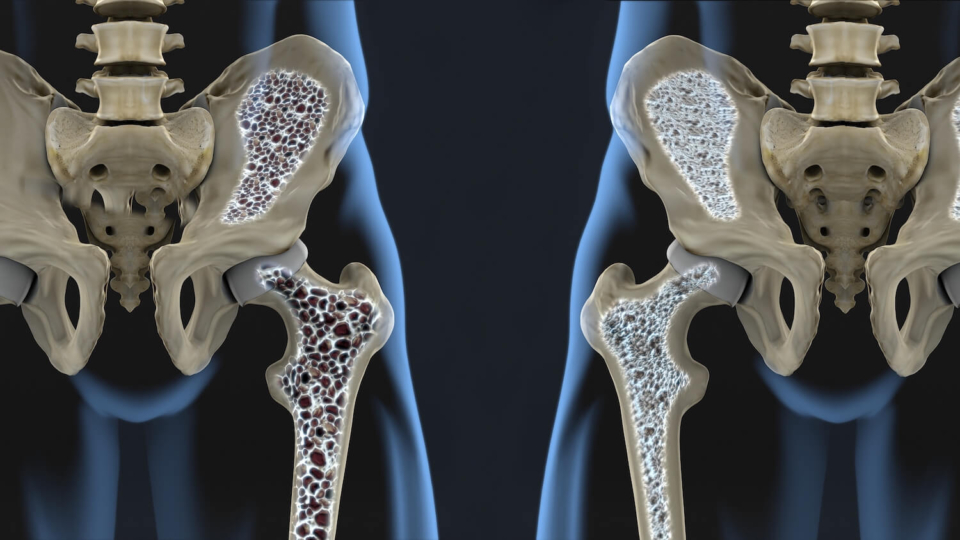

Остеопороз — це прогресуюче захворювання кісткової тканини, при якому організм втрачає кальцій та порушується структура кісток.

Кісткова тканина стає крихкою та схильною до переломів навіть при незначних травмах. Найбільш вразливим є поперековий відділ хребта, стегна і зап’ястя. Проте, найскладнішим лікарі називають перелом шийки стегна. Після такої травми кожен другий хворий на все життя залишається інвалідом, кожен четвертий помирає протягом трьох років після перелому і лише у 25% випадків пацієнти здатні повернутися до звичного життя. Особливо невтішним такий перелом є для людей похилого віку: вони до кінця життя можуть залишитися прикутими до ліжка і призвести до інвалідизації.